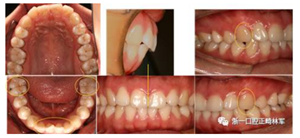

口內(nèi)檢查

2.png

恒牙列。上下頜中線對(duì)齊。上下頜牙列輕度擁擠。前牙覆合、覆蓋正常。尖牙、磨牙中性關(guān)系。上下前牙基本直立,前牙區(qū)牙根、牙槽骨較突。雙側(cè)上頜尖牙磨耗。

功能及顳下頜關(guān)節(jié)檢查:無(wú)關(guān)節(jié)壓痛及彈響,開(kāi)口度、開(kāi)口型正常。